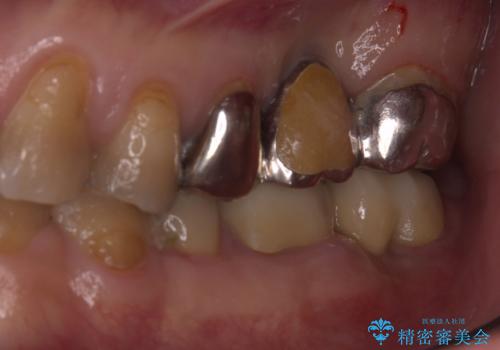

- 主訴:左上一番奥の歯の奥側にフロスを沿わせてこするといつも汚れがでてくる。

左上に保険適用の⑤ 6 ⑦ブリッジが入っており、7番目の歯と被せものとの境目に段差があり、そこに汚れが停滞したいたため適合の良いオールセラミッククラウンブリッジでのやり替えとなりました。

左上7番遠心マージン不適を認め、そこに汚れが停滞していたためやり替えをおすすめし、汚れが付着しずらく審美性に優れたセラミッククラウンブリッジでのやり替えとなりました。